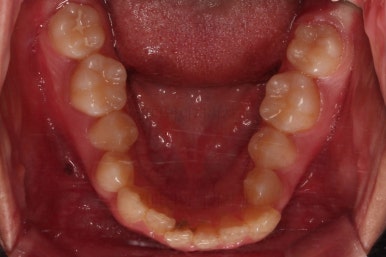

부산교정치료 초진 시 입안의 모습입니다.

치아가 전반적으로 삐뚤고, 덧니가 두드러져 보이네요.

그리고 선을 그려놨는데 윗니의 라인과 아랫니의 라인이 평행이 아니죠.

기울어 있어서 양측의 교합의 강도가 다른 상황이었습니다.